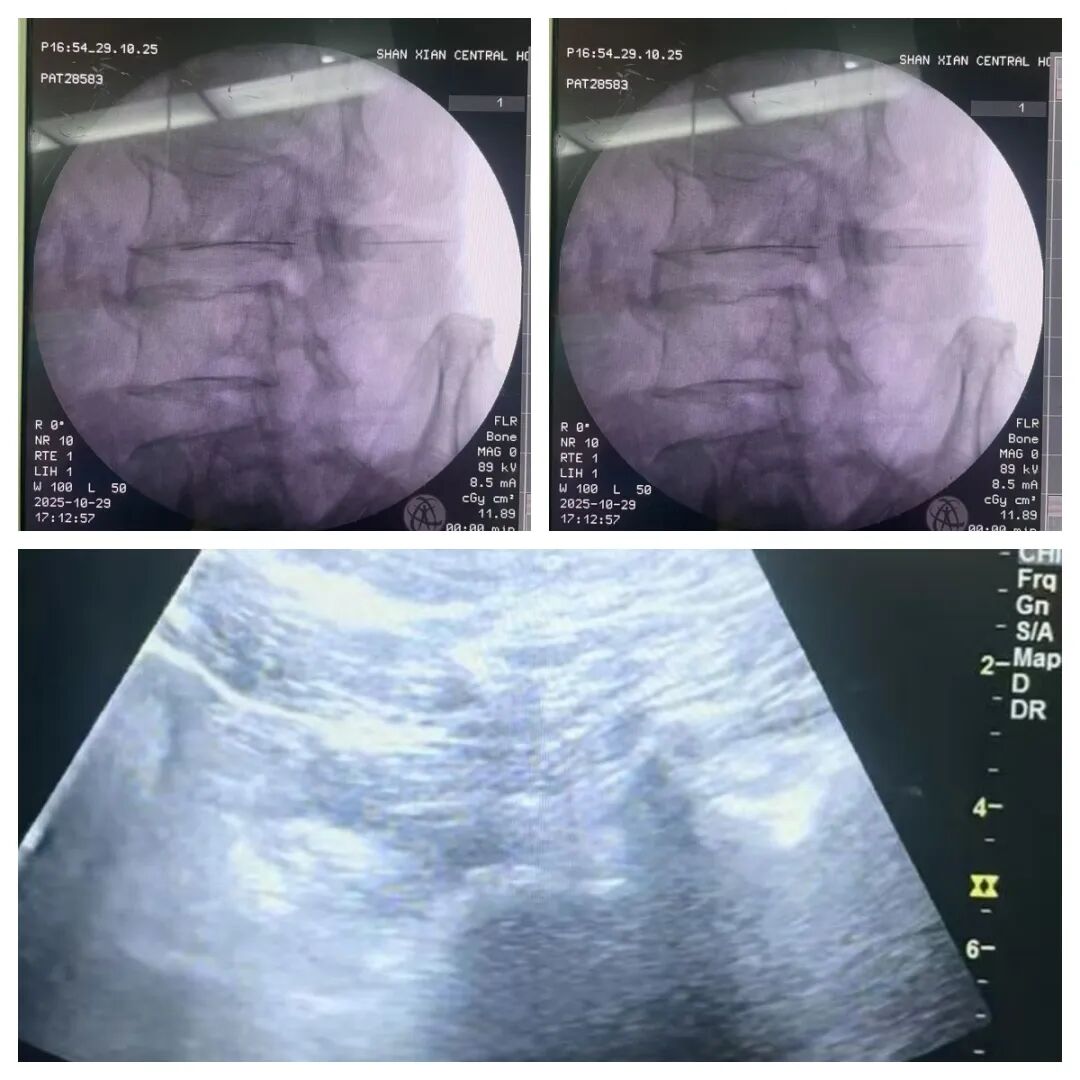

鲁网11月4日讯 近日,单县中心医院麻醉疼痛科团队联合骨科姜新强团队成功为多名糖尿病足患者实施超声联合X线引导下腰交感神经阻滞术。术后患者即刻反馈足部麻木、疼痛感缓解,皮肤温度明显上升,肢体血液循环得到有效改善,为糖尿病足的治疗开辟了精准、安全的新路径。

双引导神经阻滞术,借助超声的实时动态成像与X线的精准解剖定位,如同为手术装上“双导航”,能避开血管、神经等关键结构,将药物精准送达腰交感神经节,快速解除神经对血管的过度抑制,扩张下肢血管、改善微循环。